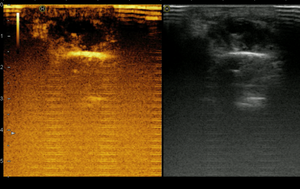

Ультразвуковое исследование мягких тканей

- Исследование в В-режиме линейным датчиком